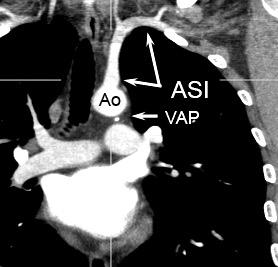

Aneurisma aórtico

Ganglios paratraqueales

izquierdos + VAP

Sarcoidosis, Metástasis, Tb, etc.

Paraganglioma

Aneurisma de arteria bronquial

Compresión por art. pulmonares.

Adenopatías región cervical y mamaria interna, prevasculares y VAP. Doble contorno aórtico.

3. Ganglios

4. Desplazamiento de la banda aorto -pulmonar. (Grasa, Adenopatías (Mets, Tb, Ca de pulmón) Hematoma intramural aórtico que sube a los troncos. Drenaje anómalo de VPSI a Vena innominada.